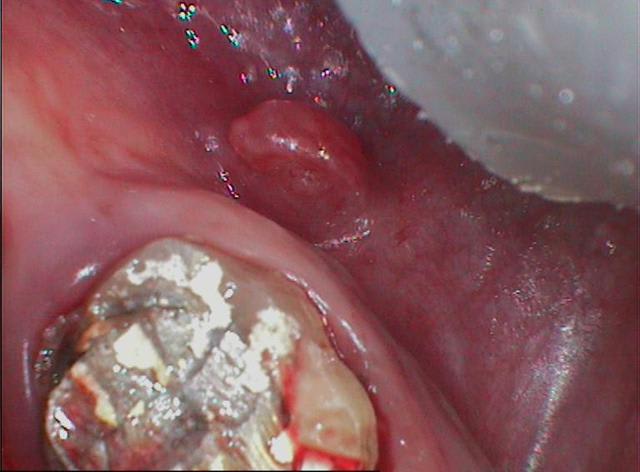

que faire ? je pense que la fistule vest vient de la prémolaire...

tenez ! cadeau

c'est le même praticien

vous noterez la position du pivot

et l'optimisme du praticien qui l'a posé dans une dent vivante

"coup de chance" ou "manque de pot" c'est à coté

je ne sais ce qui valait mieux